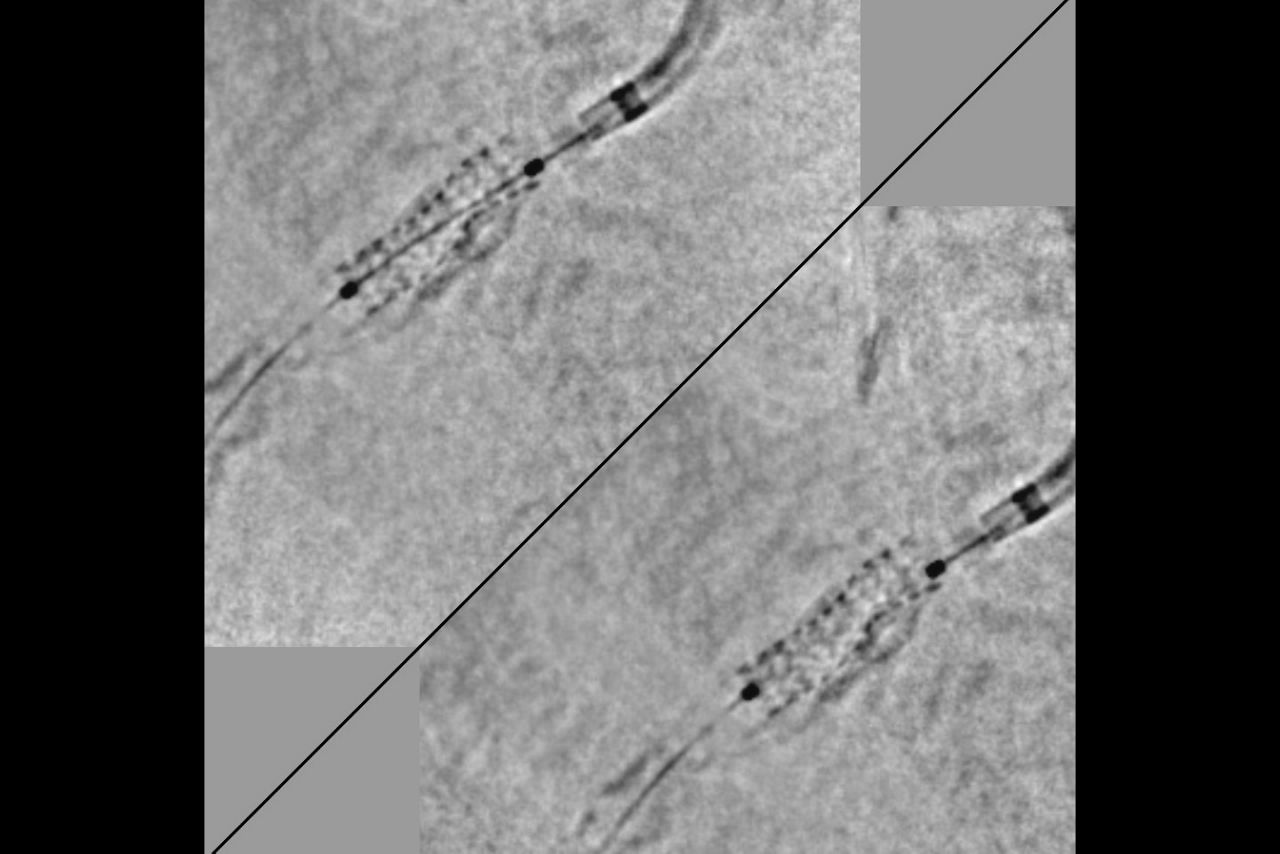

Assess

Greater precision and confidence

Clear assessment of the deployment, the apposition and the overlap.

complex_bif_SVV1